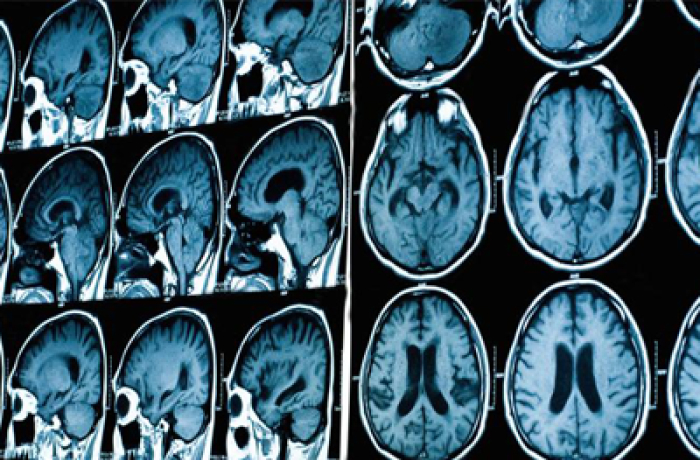

МРТ гипофиза

Гипофиз является мозговым придатком в виде округлого образования, который расположен в костном кармане на нижней поверхности мозга. Функция гипофиза заключается в выработке гормона роста, контроле работы репродуктивной системы органов и обмене веществ. При патологиях гипофиза страдает эндокринная система. МРТ гипофиза позволяет выявить даже незначительные изменения в состоянии органа и его функциональности.

МРТ имеет преимущество перед другими методами диагностики при исследовании гипофиза — несмотря на малые размеры органа, его удается исследовать с абсолютной точностью.